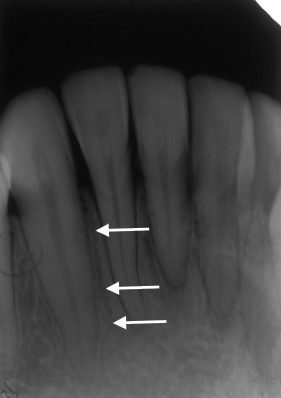

Pacjentka l. 40 zgłosiła się do gabinetu stomatologicznego z objawami nawracającego krwawienia z dziąseł w przednim odcinku żuchwy, które utrzymywały się przez okres ostatniego roku. Badaniem klinicznym stwierdzono obecność kamienia nazębnego oraz utratę przyczepu klinicznego przy zębach 31 i 41. Wykonane zdjęcie ukazało obecność struktury o charakterze przejaśnienia radiologicznego zlokalizowanego pomiędzy siekaczem bocznym o kłem (oznaczone strzałkami). Struktura ta odpowiada obrazowi: